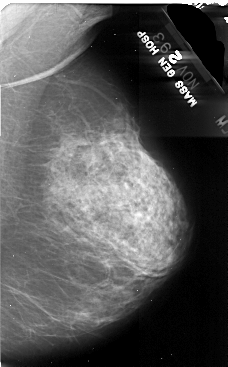

A_1078_1.RIGHT_CC

RIGHT_CC LINES 5101 PIXELS_PER_LINE 3136 BITS_PER_PIXEL 16 RESOLUTION 42 NON_OVERLAY